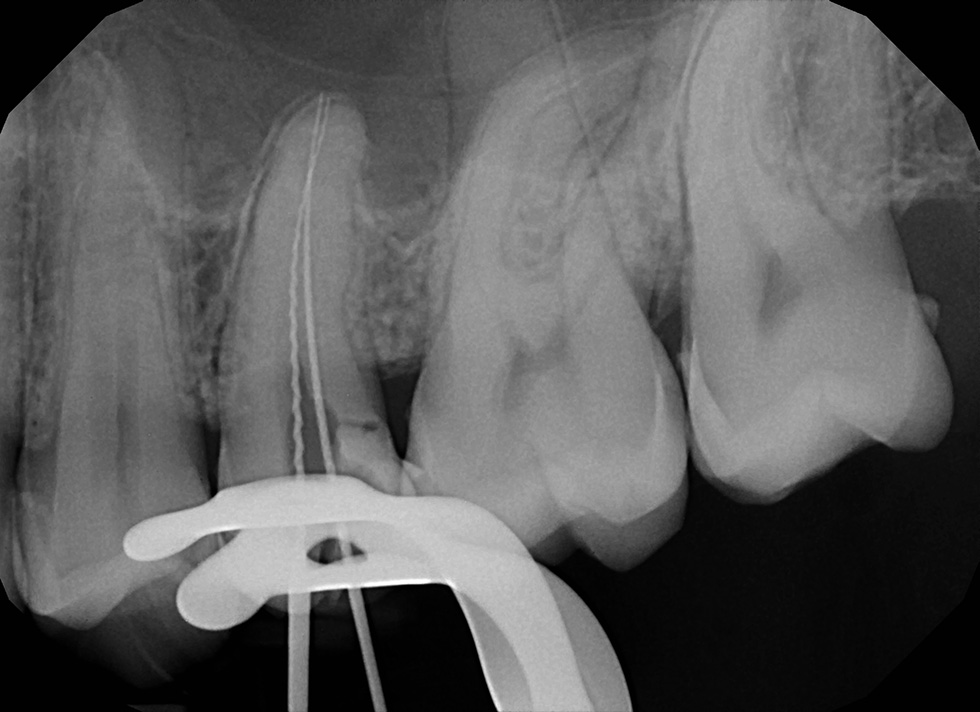

A gyökérkezelés eredményességének megállapítására a klinikai vizsgálaton kívül leginkább a képalkotó eljárások alkalmasak. A fog gyökerét vagy gyökereit, és gyökércsúcsi területét monitorozó periapicalis röntgenfelvétel alkalmas a gyökértömés, a fogágy állapotának, valamint az idő múlásával a gyökércsúcsi elváltozások gyógyulásának megítélésére.

Sikeres gyökérkezelésnek mondható ha a fog panaszmentes, csúcsig érő, falálló, jól kondenzált, jól záró gyökértöméssel lett ellátva, megfelelő koronai felépítménnyel rendelkezik, a meglévő periapicalis elváltozás gyógyulást mutat.